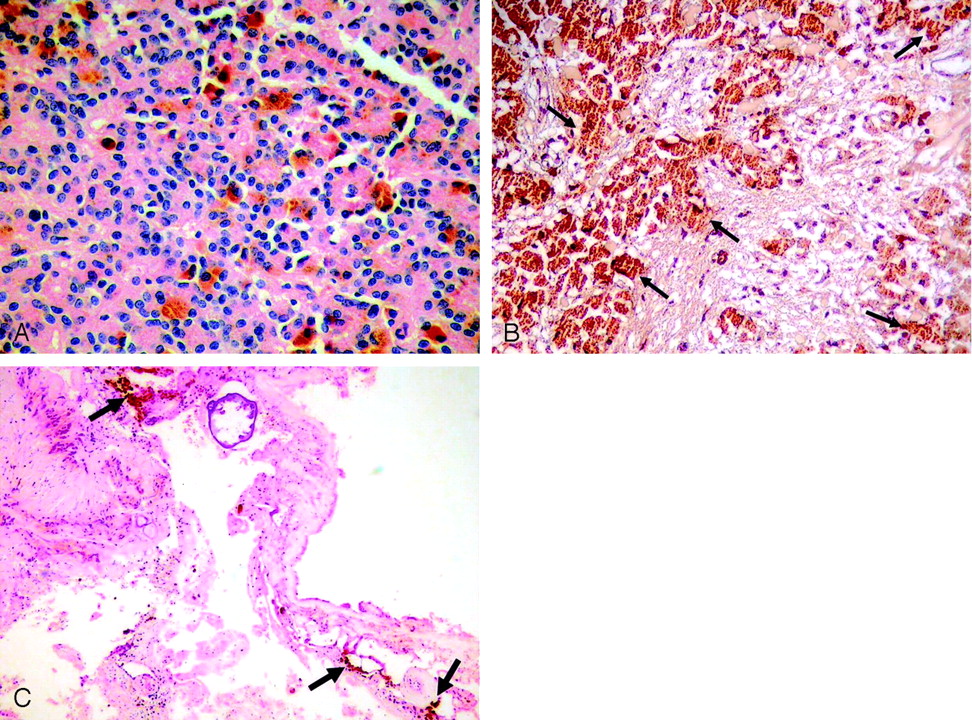

Histopathologic examination revealed typical appearance of ependymoma with true rosettes, pseudorosettes, and perivascular orientation (Fig 4A). The same tumor cells had abundant brown pigment. The brown pigment did not stain with Prussian blue and showed prominent positivity when stained with Masson-Fontana, which is a characteristic of melanin that was scattered throughout the ependymoma (Fig 4B). The immunohistochemical pattern of this tumor included positivity for glial fibrillary acidic protein, which is important in the exclusion of other melanotic diseases such as meningeal melanocytomas.

A, Microscopy shows characteristic histopathologic features of ependymoma with true rosettes and pseudorosettes, perivascular orientation (hematoxylin-eosin; original magnification × 200). B, Tumor cells have abundant brown melanin pigment (arrows) in the cytoplasm that shows positivity for Masson-Fontana (original magnification ×100). C, Brown melanin pigment is also present in the interstitial space of the tumor (arrows; hematoxylin-eosin; original magnification ×40).

The diagnosis was a melanotic ependymoma of the posterior fossa. Brown pigment was also found in the interstitial spaces and did not stain with Prussian blue but showed prominent positivity when stained with Masson-Fontana, which means releasing of melanin outside of the tumor (Fig 4C). Pial melanin accumulation secondary to posterior fossa melanotic ependymoma explained the reason why pial surfaces were hyperintense on T1-weighted images and hypointense on T2-weighted images. The patient’s condition progressively worsened, and he died 12 days after surgery.